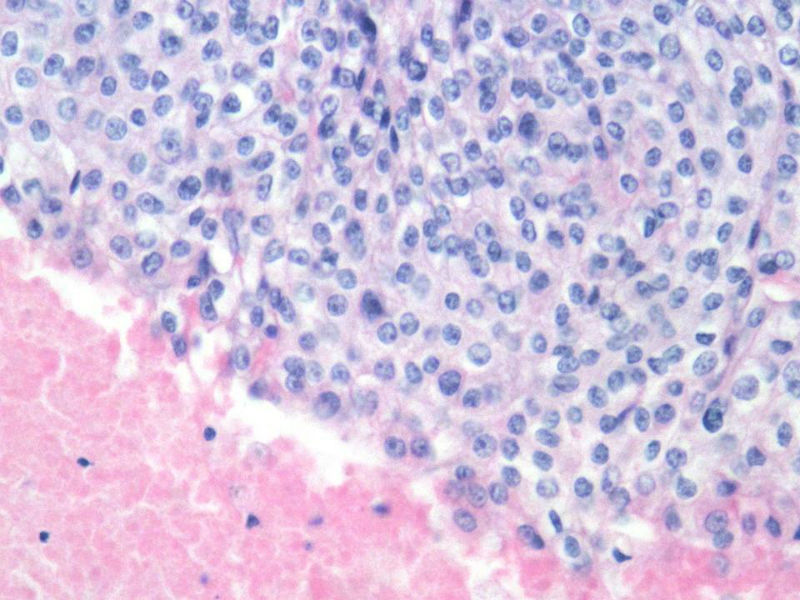

女,64岁,头晕半月,CT检查颅内左颞叶占位,侵犯颅骨和颞肌,手术切除肿物。肉眼,灰白色结节状肿物,3X3X2厘米,边界不清,切面灰黄色,质软。

特别提示:手术前曾做过介入肿瘤栓塞。镜下核分裂15/HP。脑左颞部占位图1

梭形细胞与上皮样漩涡状结构,富于细胞,见个别沙砾体,并见肿瘤性坏死。颅骨及其横纹肌等软组织内见肿瘤呈侵袭性生长。但细胞异型性不是很大。鉴别:

1)恶性脑膜瘤

2)非典型性脑膜瘤

由于非典型性脑膜瘤也可以发生地图状坏死,甚至侵袭性生长。需要计数核分裂数/10HPF,以资鉴别诊断。